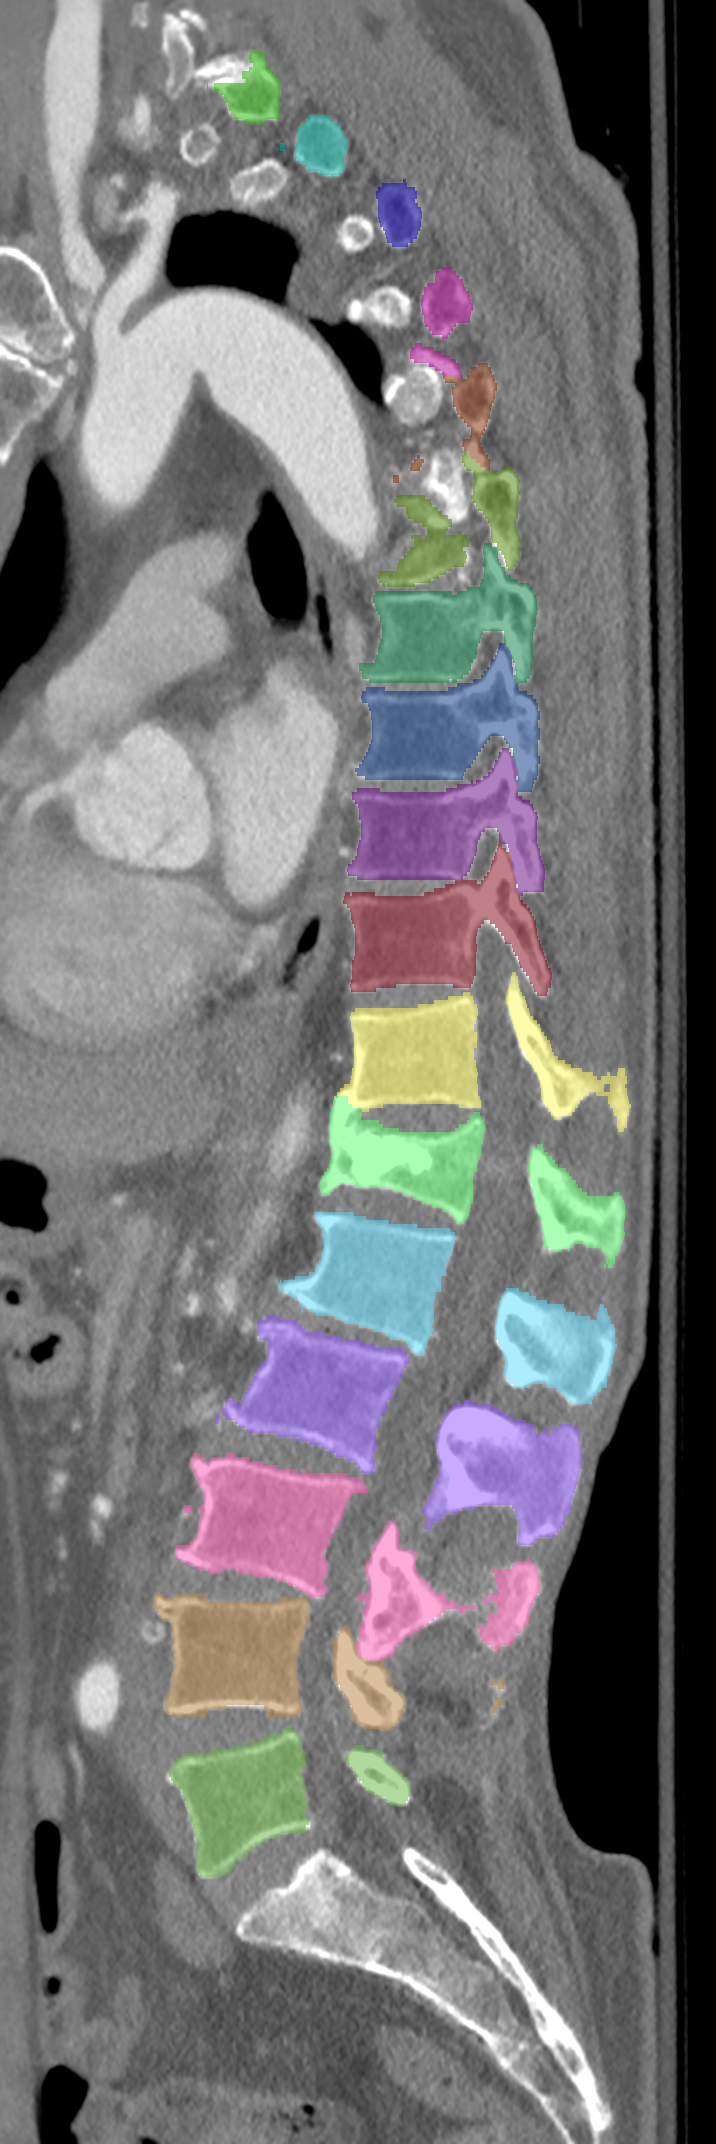

Normalized CT images and reference segmentations of thoracic and lumbar vertebrae from the CSI 2014 workshop

This is the dataset of the vertebra segmentation challenge of the CSI 2014 workshop that was held in conjunction with MICCAI 2014.

- 16-20: Test set, scans of 5 patients with vertebral compression fractures

- Vertebrae have been anatomically labeled (8 = T1, 9 = T2, ..., 24 = L5)

The resolution and segmentation quality of the diseased cases (16-20) is quite low.